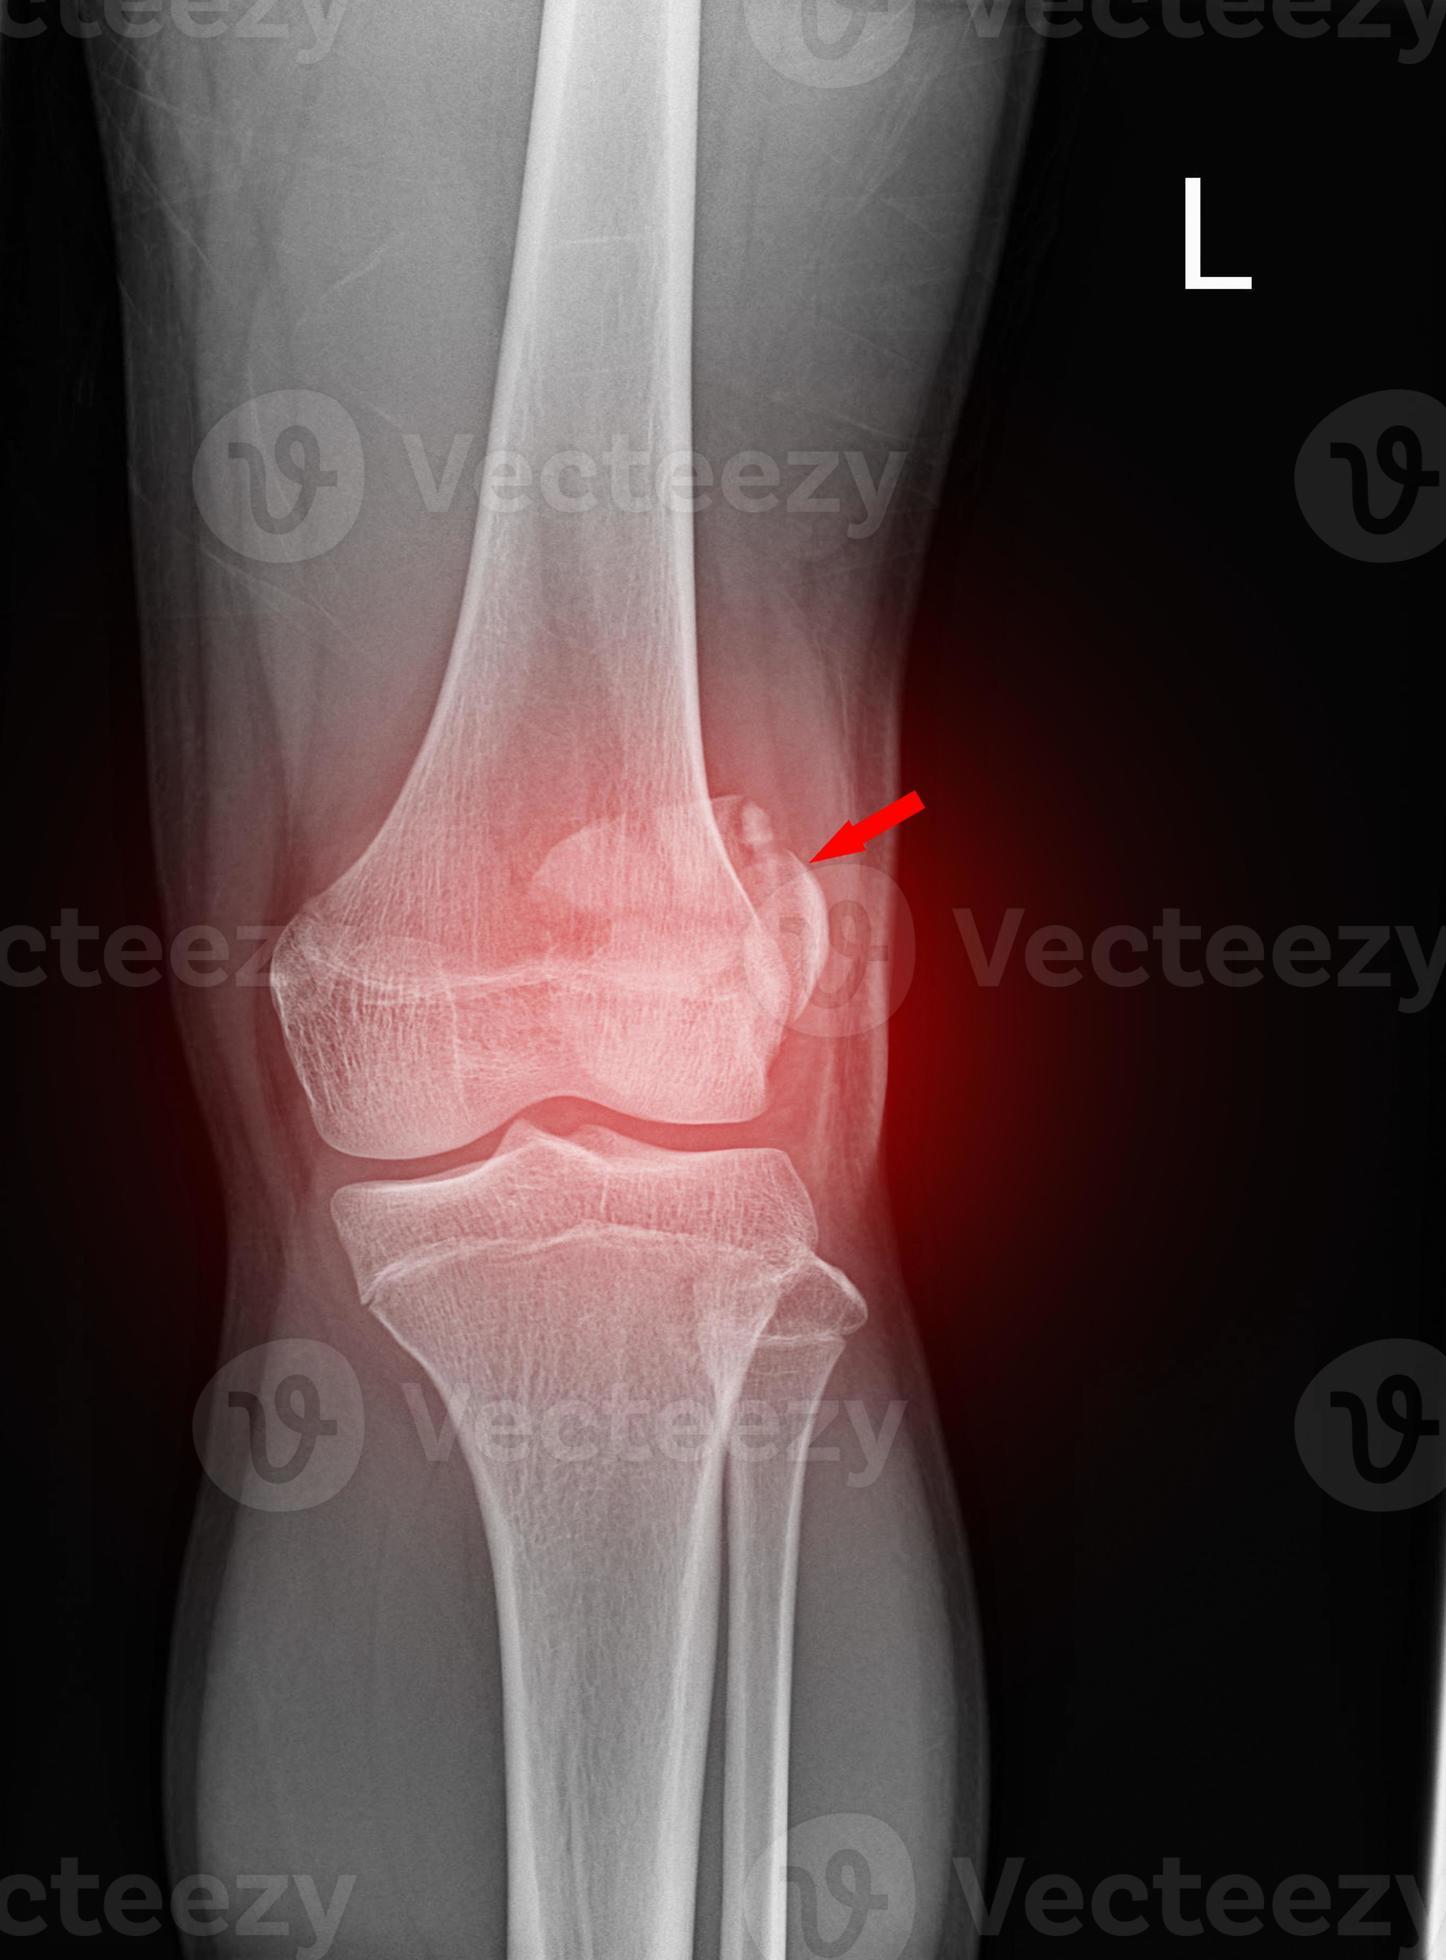

From www.vecteezy.com

A film xray of left knee lateral view shown fracture of knee cap Compression Fracture Knee Cap patella fractures are caused by direct trauma or compressive force, or as the indirect result of quadriceps contractions or excessive stress to the extensor. Fractures of the patella are most often caused by a direct blow to the knee, such as a fall or motor vehicle. patella fractures are traumatic knee injuries caused by direct trauma or rapid. Compression Fracture Knee Cap.